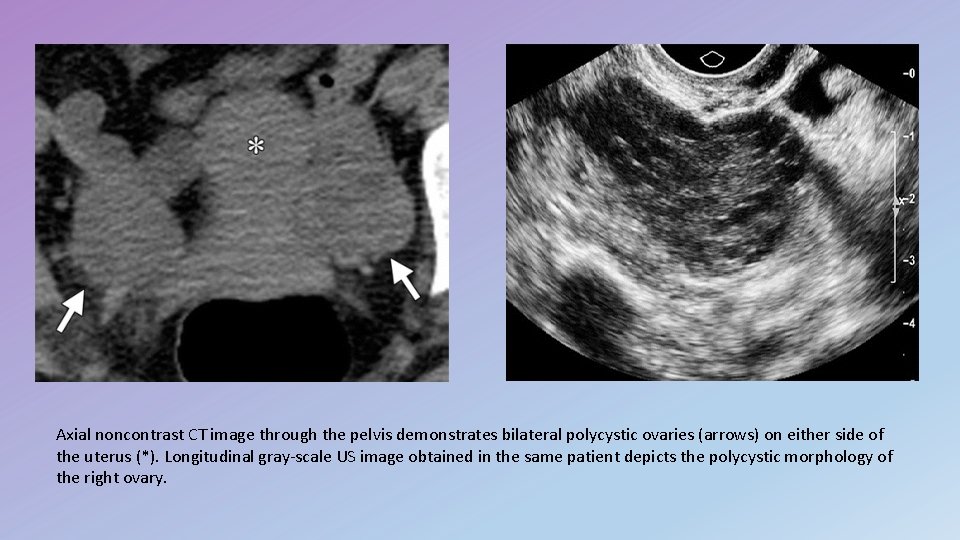

Use of CT scan for the assessment of PCOS • CT is not used in the evaluation of patients with possible PCOS, since the internal ovarian structure is far better depicted at US or MR , • polycystic ovaries may sometimes be seen in such patients when they undergo CT for other reasons.

Axial noncontrast CT image through the pelvis demonstrates bilateral polycystic ovaries (arrows) on either side of the uterus (*). Longitudinal gray-scale US image obtained in the same patient depicts the polycystic morphology of the right ovary.